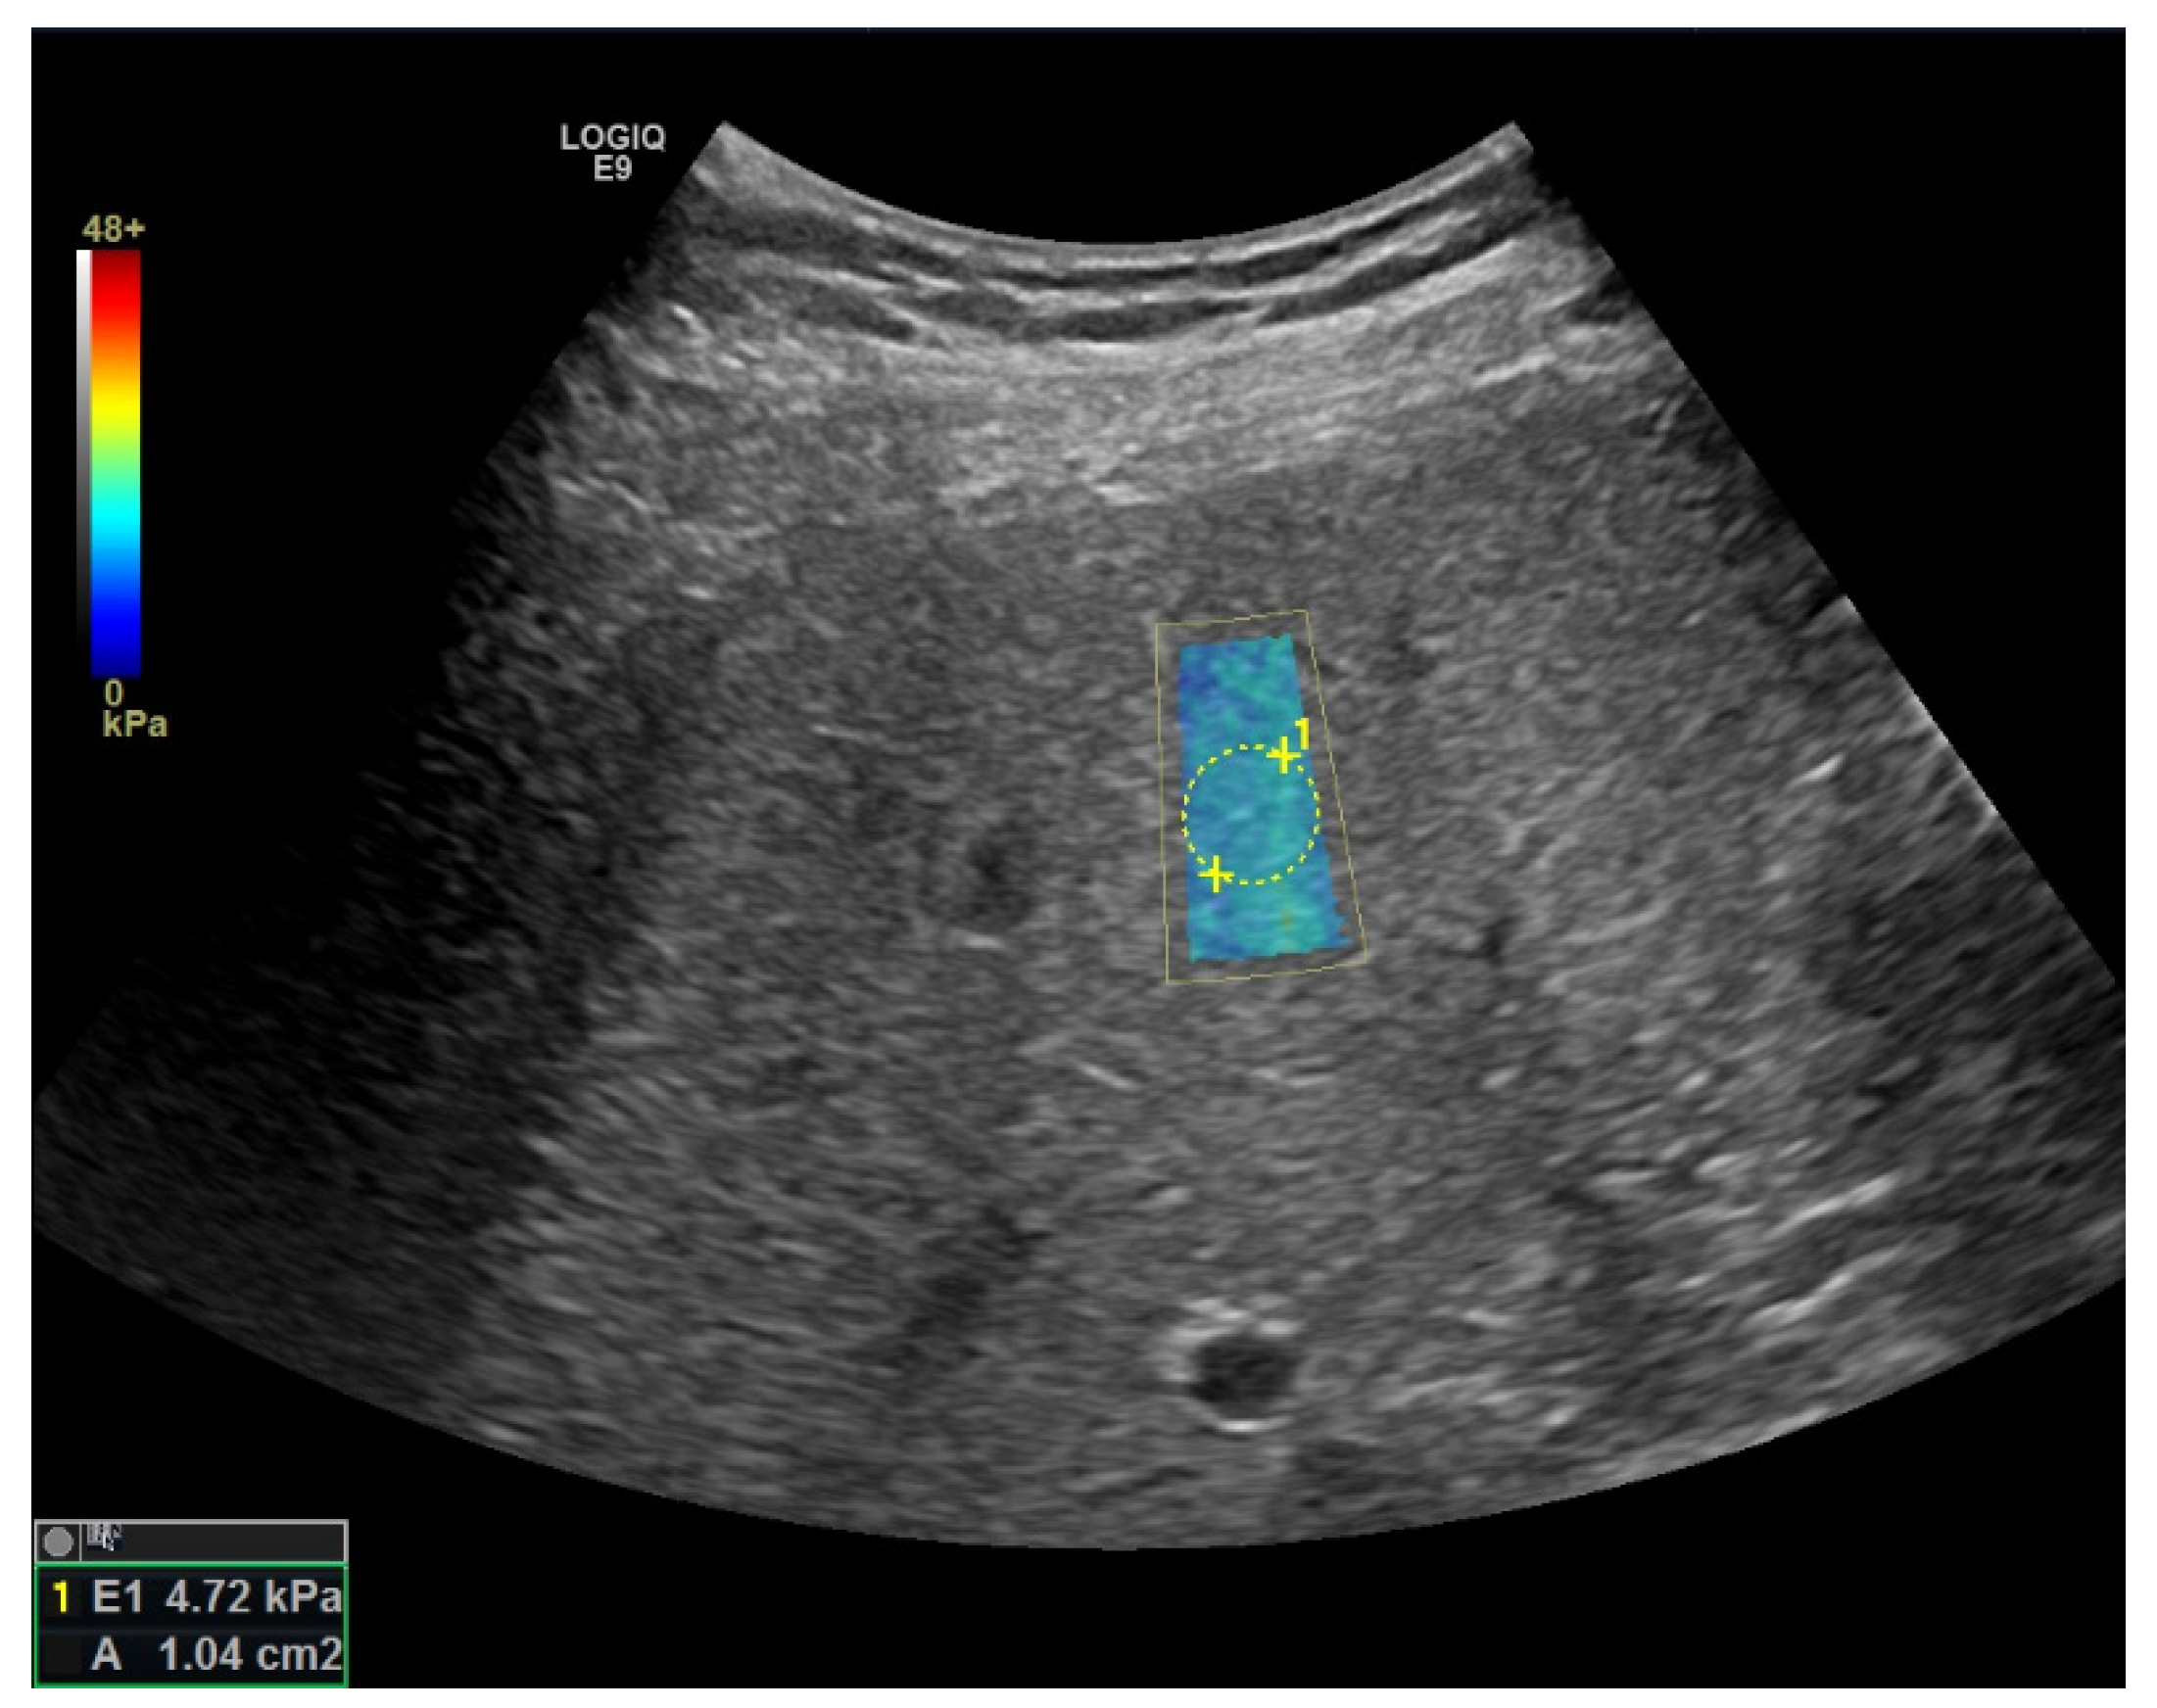

Elastography